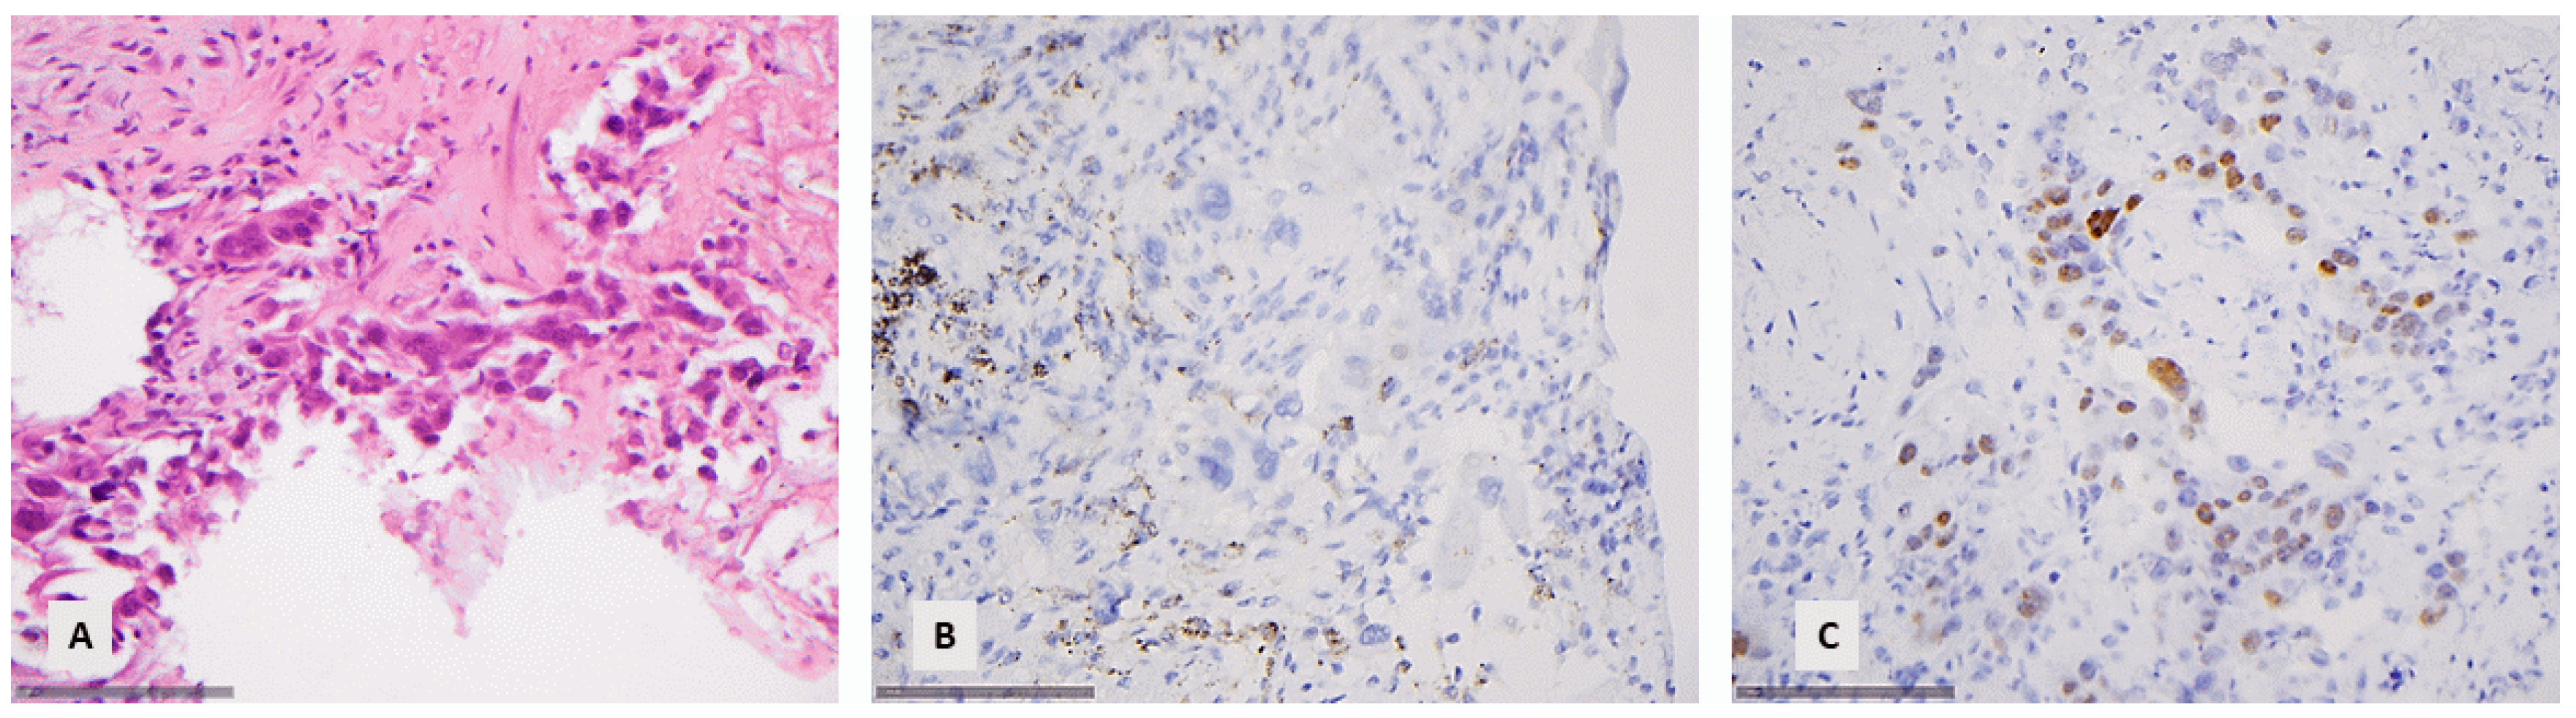

Figure 6. A NSCLC with extensive expression of p63 and negativity for p40 ((A) HE, ×400, (B) p40, ×400, (C) p63, ×200).

3.8. Comparison of p40 with p63

There was a statistically significant difference between the expression levels of p63 and p40 (Student t-test, p < 0.001, Chi-square test < 0.001). In particular, 53% of the cases were negative for p40, 10.6% showed a minimal expression (<10%), 4.6% a moderate expression (10–50%), and 31.8% an extensive expression (>50%). On the other hand, 39.7% of the cases were negative for p63, 15.6% showed a minimal expression (<10%), 7.5% a moderate expression (10–50%), and 37.2% an extensive expression (>50%). Importantly, among the 104 p40-negative cases, 32 displayed a positive p63 immunoreactivity (30.7%), 22 showed a minimal expression (<10%), 7 a moderate expression (10–50%), and 3 an extensive expression (>50%) (Figure 6).

No difference was observed in the level of p40 and p63 expression for the SCC group (Student t-test, p > 0.10), but the difference was found to be statistically significant for the subgroup of ADC (Student t-test, p < 0.001) or NSCLC NOS (Student t-test, p = 0.007), with p63 having the tendency to display higher levels of immunohistochemical expression compared with p40. However, in none of the investigated cases would this difference be able to change the final histological diagnosis. In the absence of p40 immunoreactivity, p63 expression was either accompanied by mucin production or TTF-1 expression, leading to the correct diagnosis of ADC, or it was not so extensive (<50%), thus leading to the diagnosis of NSCLC NOS.